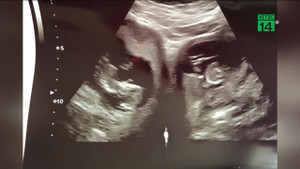

Một bà mẹ ở Anh mang song thai, đặc biệt người mẹ này có tới tận 2 tử cung, và mỗi em bé lại nằm ở một tử cung độc lập.